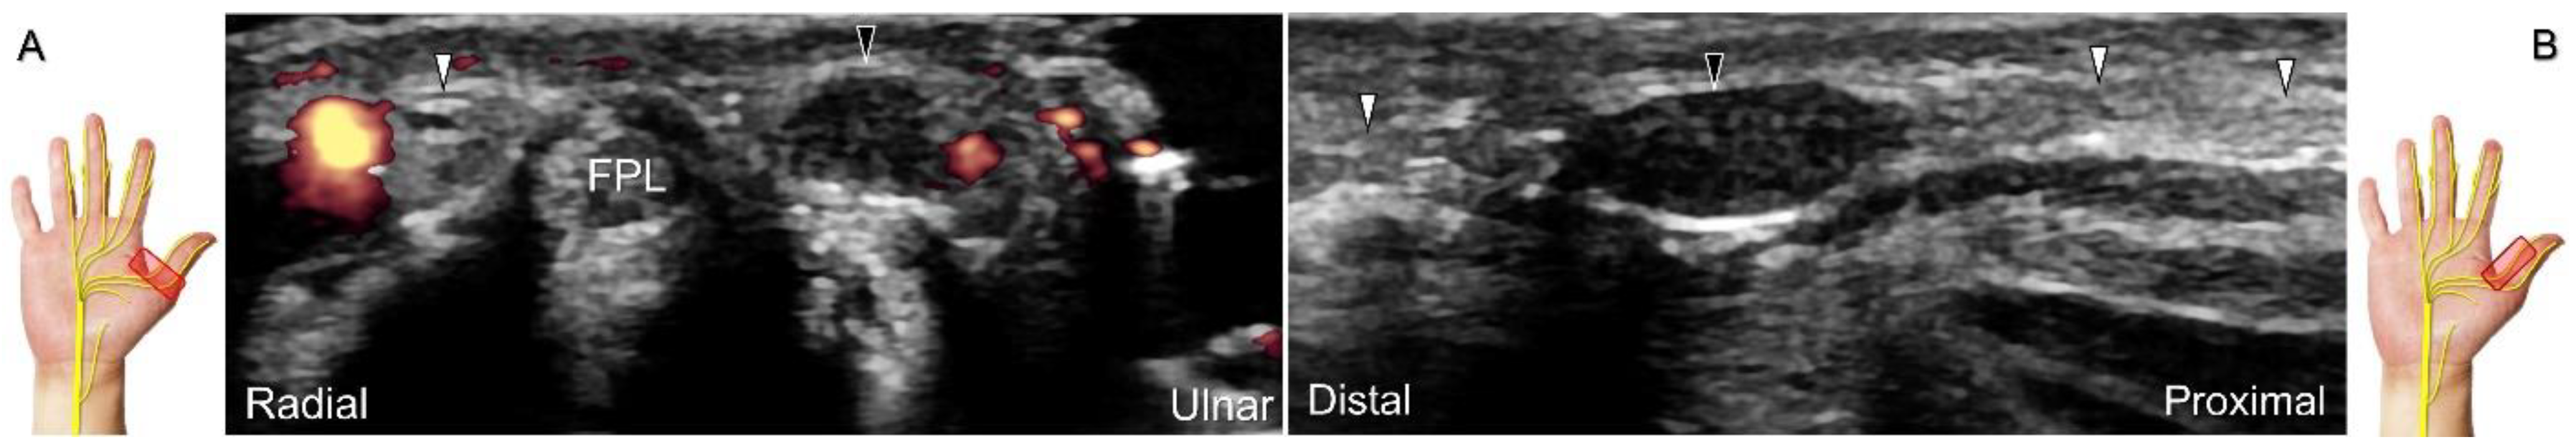

3.1.3. Recurrent Motor Branch of the Median Nerve

The recurrent motor branch of the median nerve innervates the thenar muscles, i.e., abductor pollicis brevis, opponens pollicis, and the superficial head of the flexor pollicis brevis. There are four main types of reciprocal anatomy between this branch and the transverse carpal ligament. The mean diameter of the recurrent motor branch has been reported as 0.7 mm—with a standard deviation of 0.1 mm in healthy volunteers [33]. The extraligamentous type is the most common [34,35], where the nerve emerges from the main trunk distal to the carpal tunnel outlet, ascends vertically to the palmar surface through the distal edge of the transverse carpal ligament [36], and then curves back to innervate the thenar muscles. However, if the recurrent motor branch exits the main trunk in other locations, the nerve is classified as preligamentous, subligamentous, or transligamentous, depending on whether it exits proximal to the flexor retinaculum, within the carpal tunnel, or by piercing the transverse carpal ligament, respectively [35].

Scanning Technique

To assess the median nerve and its branches, the transducer is initially placed over the carpal tunnel inlet and then moved distally/radially. In the extraligamentous type, the recurrent motor branch emerges from the radial aspect of the median nerve as it travels distally to the carpal tunnel outlet. However, at this point, identifying the precise site of branching may be challenging due to anisotropy and the nerve’s reversed course. To aid visualization, the physician can pivot the radial end of the transducer back and forth to identify the recurrent motor branch. It appears as a hypoechoic monofascicle that pierces the palmar aponeurosis, reaching the surface of the thenar muscle (Figure 10). Occasionally, other anatomic variants can also be visualized (Figure 11) [37].

Clinical Implication

The recurrent motor branch may be injured during carpal tunnel release, trigger point injection of the thenar muscle, and repetitive impact of the thenar eminence [34]. In the case of nerve injury, the thenar muscle is likely to undergo atrophy, leading to a subsequent reduction in pinch and grasp forces. US reveals a swollen fascicle and an indistinct border of the injured nerve, with poor visualization of the epineurium (Figure 12; Video S3). US-guided hydrodissection in short-axis view has been reported helpful for reducing thenar pain in a case with recurrent motor branch entrapment [36].

Figure 10. Sonographic imaging for the recurrent motor branch of the median nerve. Tracking back from the surface of the thenar muscle (A) toward the division site from the main trunk in short-axis (B) and long-axis (C) imaging. Asterisk: median nerve; white arrowheads: recurrent motor branch of the median nerve; a: artery; FPL: flexor pollicis longus tendon; FPB: flexor pollicis brevis muscle.

Diagnostics 13 01928 g010

Figure 12. Sonographic imaging (short-axis view) shows the segment (A) distal to the neuroma of the recurrent motor branch of the median nerve (B) and the proximal segment (C). Asterisk: median nerve; white arrowhead: recurrent motor branch of the median nerve; black arrowheads: neuroma. FPB: flexor pollicis brevis muscle; AbP: abductor pollicis brevis muscle.

Diagnostics 13 01928 g012